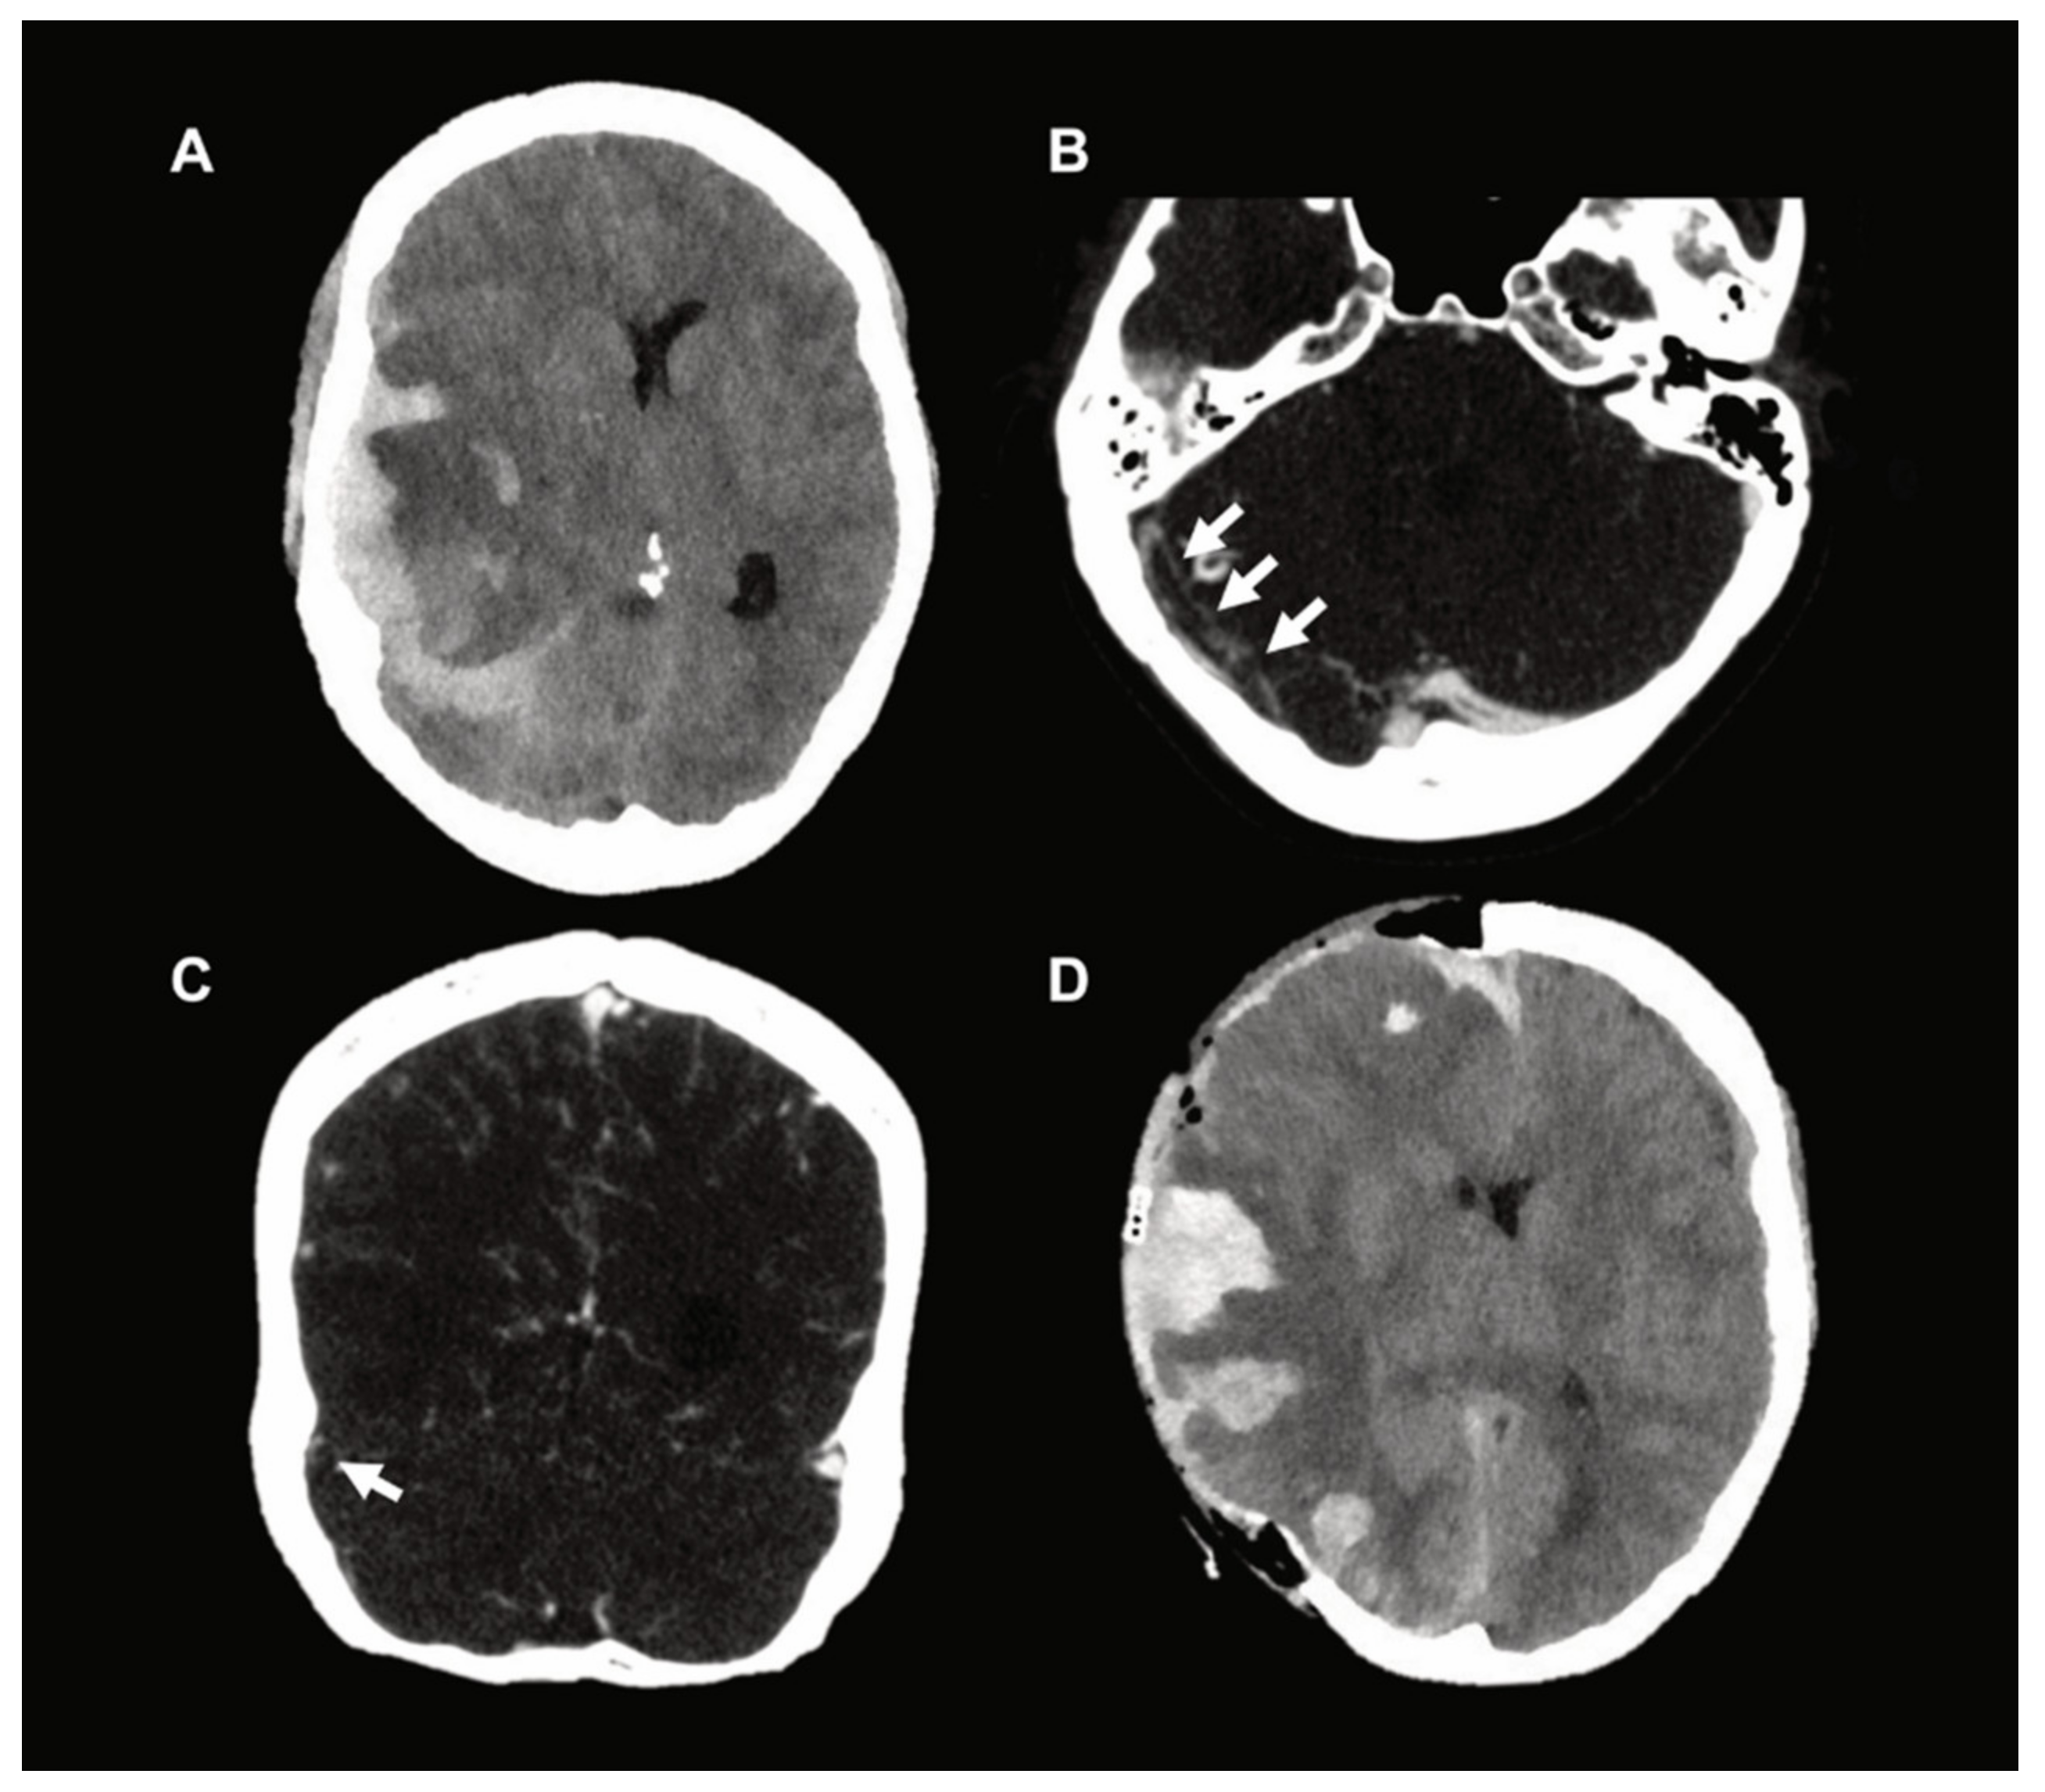

2. Exemplary Case Presentation